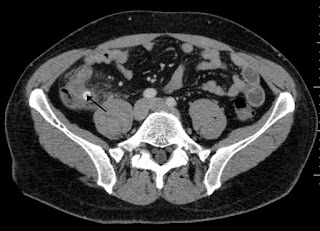

This single-centre randomized non-inferiority trial found that low-dose abdominal CT was non-inferior to standard dose in terms of negative appendectomy rates with an absolute increase of 0.3% in the low dose group (0.3, 95% confidence interval -3.8 to 4.6). The group felt this was not a practice changing study, as it did not include obese patients; there was a high risk of bias as the interpreting radiologists were not blinded, and it was not applicable to our clinical practice in Canada where we often obtain an ultrasound before CT.